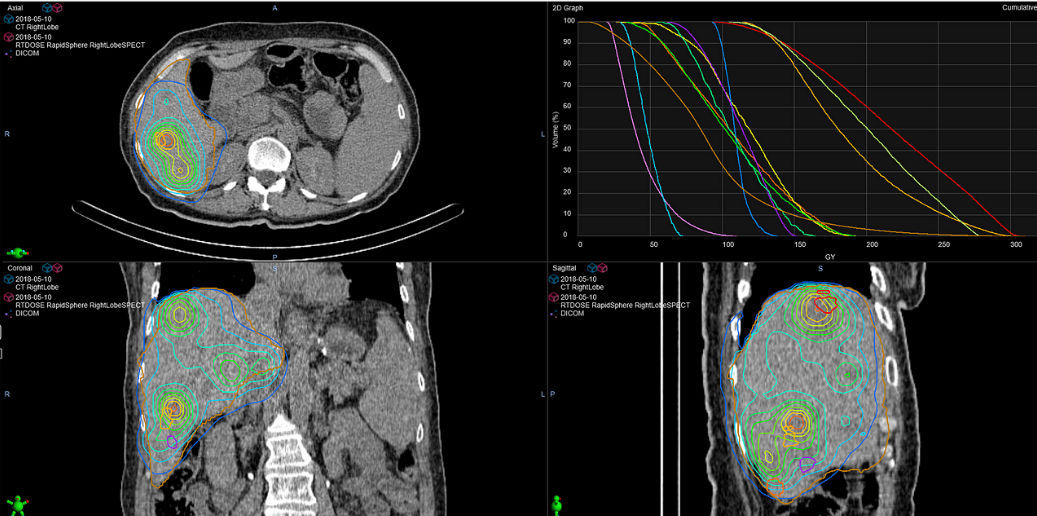

From www.medicalexpo.com

Medical software RapidSphere Varian Oncology oncology / treatment / modeling Varian Medical Systems India Software From software and machines to patient data and care teams, intelligent cancer care is uniting the world's cancer fight. Fortis international oncology centre, a joint initiative between international oncology and fortis healthcare, is equipped with advanced. We offer a wide range of software solutions to help meet your clinical needs.varian’s comprehensive oncology software provides a. Varian medical systems international (india). Varian Medical Systems India Software.